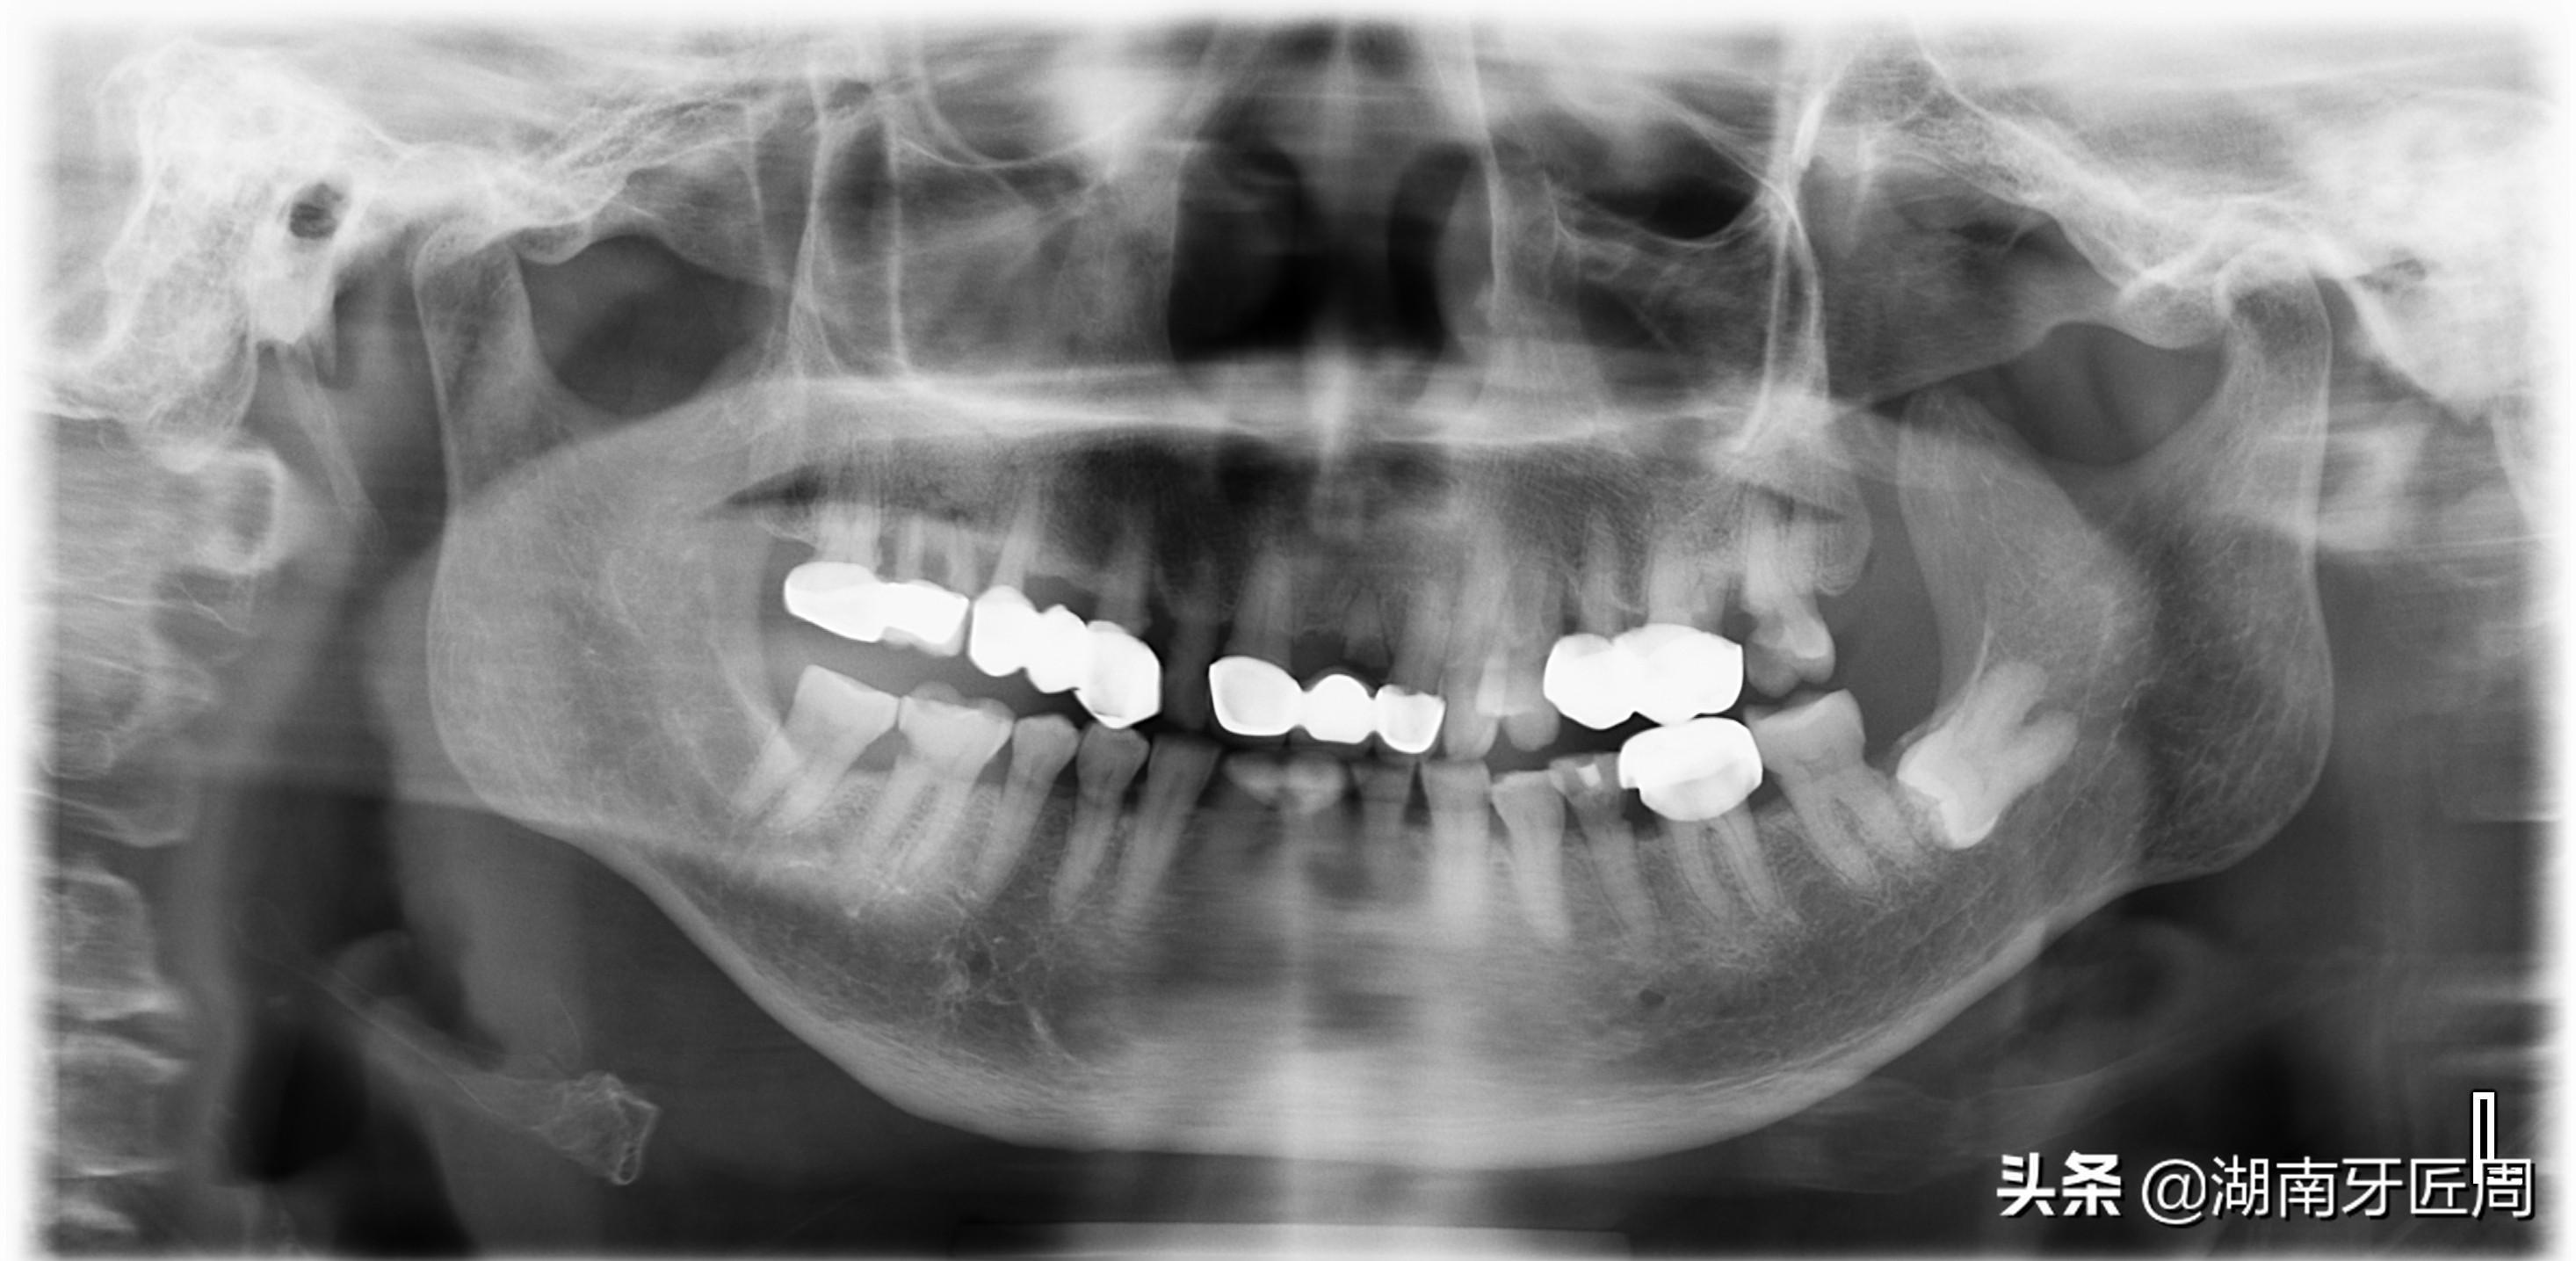

左侧智齿倾斜阻生,顶坏前牙

图片2.右侧智齿倾斜阻生顶坏前牙